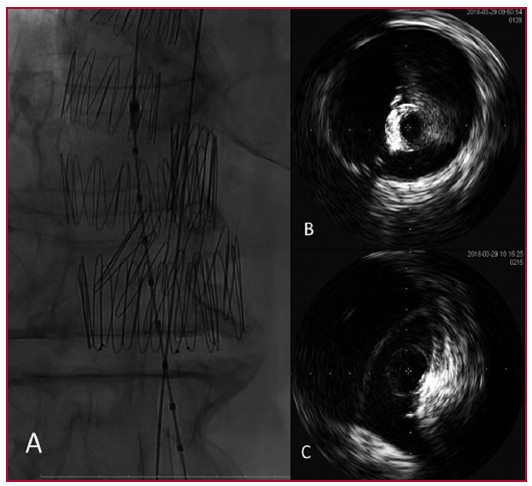

Mediante control con IVUS se desplegó la extensión aórtica en la falsa luz, exactamente a la altura del extremo distal de la endoprótesis previa colocada en la luz verdadera (Fig. 1). Finalmente, se colocó un Amplatzer Vascular Plug II de 22 mm (AGA Medical Corp., North Plymouth, MN, EE. UU.) en el centro del tapón para completar la oclusión. La angiografía final no mostró flujo retrógrado residual en la luz aneurismática.

Fig. 1. A. Imagen angiográfica intraoperatoria que muestra la endoprótesis torácica en la luz verdadera y el tapón (endoprótesis en forma de copa invertida) en la luz falsa. B. Imágenes de ecografía intravascular, tanto desde la luz verdadera como desde la falsa, mostrando la presencia de flujo, sitio de despliegue del tapón y origen del tronco celíaco

Un detalle técnico de importancia fue, además, la utilización de la ecografía intravascular. Dicha técnica es beneficiosa, especialmente en pacientes con disecciones crónicas, con múltiples orificios de entrada y reentrada. Asimismo, la ecografía intravascular nos permitió verificar el nivel exacto al que debían abrirse las endoprótesis, para evitar ocluir ramos viscerales. Especialmente en este caso, seleccionamos también el orificio de reentrada apropiado para introducir el dispositivo oclusor.